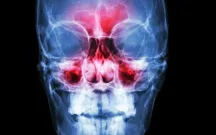

Management of CRSwNP in Latin America: A multidisciplinary consensus from an expert working group

Se convocó a un panel de expertos de América Latina para desarrollar una guía regional sobre el manejo de CRSwNP a través de un enfoque de consenso. El presente artículo presenta las principales observaciones y recomendaciones que pueden servir de guía para los médicos de la región latinoamericana.